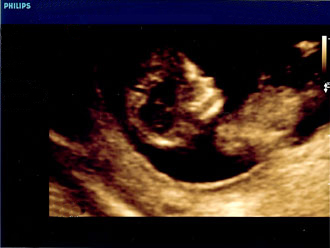

Kind gesund und lässig! - Tagebücher aus der Schwangerschaft von Julia aus Göttingen

Eine neue wunderbare, aufregende und vielleicht auch lang erwartete Lebenszeit beginnt. Für unsere Tagebücher-Blogs haben wir immer 3-4 schwangere Frauen in unterschiedlicher Schwangerschaftsphase, die in freudiger Erwartung über jede Woche dieser spannenden Zeit schreiben, uns und die vielen tausend Follower:innen daran teilhaben lassen und damit unvergessliche Momente schaffen.